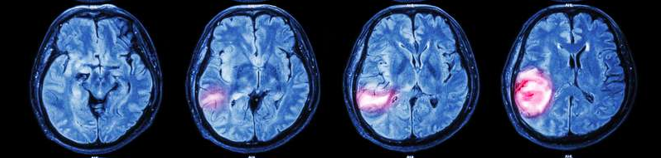

腦腫瘤是怎么樣一個(gè)發(fā)展進(jìn)程?以下兩個(gè)gif圖帶你看懂 (從左到右分別為腦腫瘤初始,1個(gè)月后,6個(gè)月后,1年后) (從左到右分別為腦腫瘤初始,4個(gè)月后,6個(gè)月后,1年后,1年半后)...

(從左到右分別為腦腫瘤初始,1個(gè)月后,6個(gè)月后,1年后)